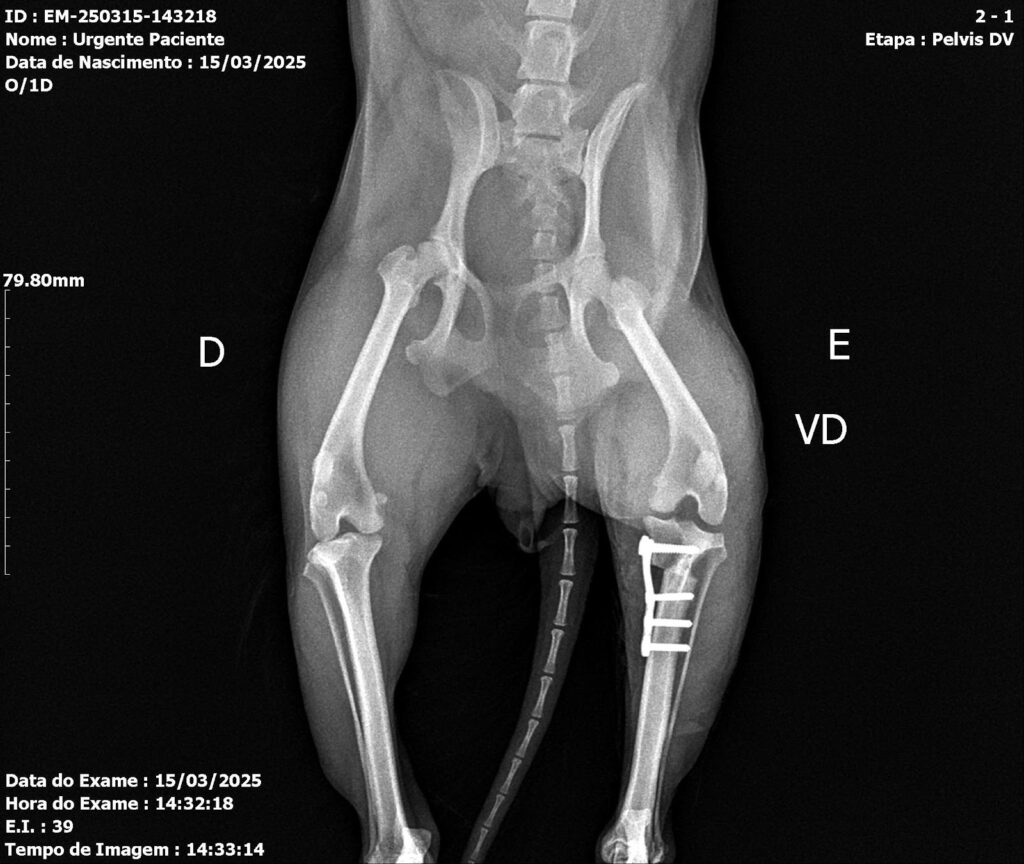

Postoperative evaluation included assessment of range of motion, limb alignment, and joint stability. Radiographs confirmed appropriate implant positioning and patellar alignment (Figures 4 and 5). A slight reduction of the medial femorotibial joint space was noted, with preservation of overall congruence. Mild lateral displacement of the patella was observed on the craniocaudal view and minimal caudal displacement on the mediolateral view. Increased soft-tissue opacity and volume, compatible with postoperative inflammatory changes, were also identified. The semicircular osteotomy in the proximal third of the left tibia and adequate implant positioning confirmed correct surgical execution.

Figures 4 and 5: Ventrodorsal and mediolateral radiographs of the left pelvic limb in the immediate postoperative period, showing fracture stabilization using an orthopedic plate and screws, with proper bone alignment.